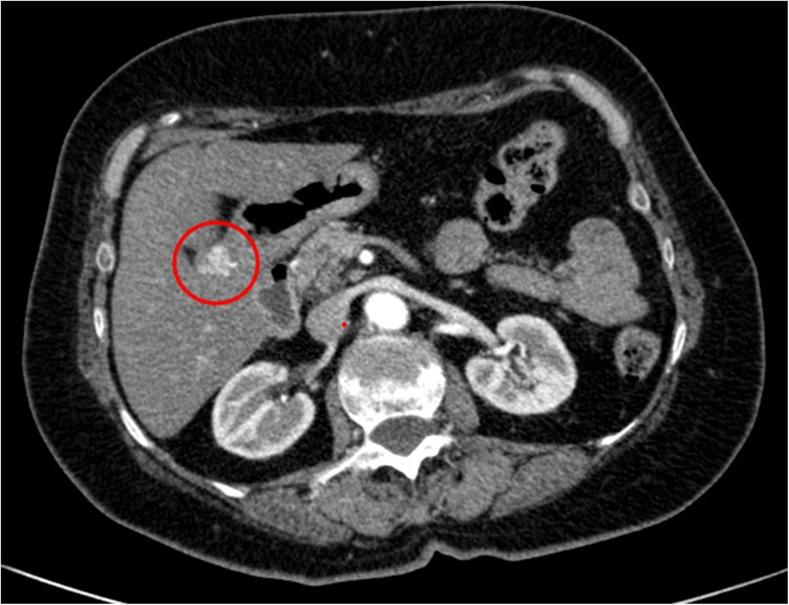

Glomus Tumor of the Stomach: GI Image.

Glomus Tumor of the Stomach: GI Image.胃血管球瘤:胃肠道影像